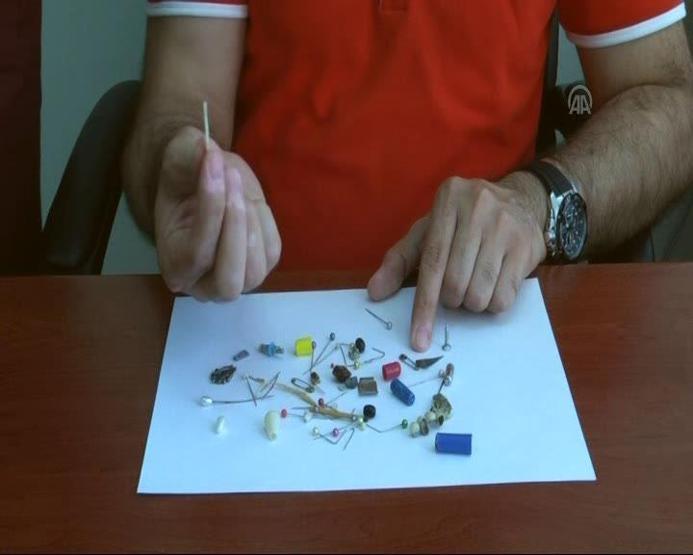

Cumhuriyet Üniversitesi (CÜ) Tıp Fakültesi Araştırma ve Uygulama Hastanesi Göğüs Cerrahisi Anabilim Dalı Servisi'nde insanların yanlışlıkla yuttuğu cisimlerden oluşturulan koleksiyon, görenleri hayrete düşürüyor. İğne, metal kolye, vida, protez diş, dikiş iğnesi, kemik parçası, pisi pisi otu, çivi ve akasya dikeni gibi bu cisimlerden koleksiyon yapan hekimler, vatandaşların ağızlarına aldıkları şeylere dikkat etmeleri ve herhangi bir cisim yutulması halinde vakit kaybetmeden hastaneye başvurması gerektiği konusunda uyarıyor.

Operasyonlarda çok tuhaf yabancı cisimlerle karşılaştıklarını ve şaşırdıklarını anlatan Şahin, "Çıkardığımız bu cisimlerin bir kısmını servisimizde biriktiriyoruz ve bir koleksiyon oluşturduk. Yıllardır çıkardıklarımız biriktirdiklerimizin 20-30 katı kadar" dedi.

Prof. Dr. Şahin, çıkardıkları cisimler arasında iğneler, metal kolyeler, vidalar, protez dişler, dikiş iğneleri, kemik parçaları, pisi pisi otları, çiviler ve akasya dikeni bulunduğunu kaydetti.

Yutulan cisimler arasında en çok iğne bulunduğunu dile getiren Prof. Dr. Ekber Şahin, fındık ve fıstık gibi çerezlerin de nefes borusuna kaçmasına sıklıkla rastladıklarını ifade etti.

İnsanların, midesinden ve nefes borusundan çıkan cisimleri anı olarak sakladıklarını söyleyen Şahin, "Hepsi olamasa da bir kısmını anı olarak saklıyoruz. Zaten organik olanları saklama şansımız yok. Her bir vakanın bizde ayrı ayrı anısı vardır. Her hastayı hatırlarız, hikayeleri farklı farklıdır. Böyle bir koleksiyon oluşturmaya devam ediyoruz" diye konuştu.